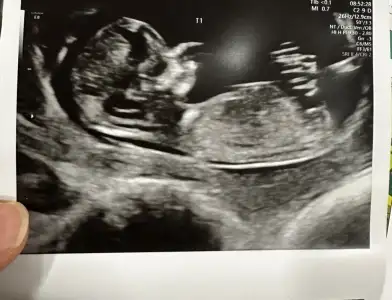

Seni de doktor benim gibi 3 haftada bir çağırıyor. Herkesi 4 haftada bir çağırmış. Muhtemelen ikimizin de daha önce benzer bi kaybı olduğu için. İnşallah sağ salim alırız hepimiz bebişleri kucağımızaMerhaba kızlar ben çıktım doktordan. Önceki gebeliğimde bebeğin kalbi durmuştu 7+3'te. Bunda da 6+1de duymuştuk kalbini aradan 3 hafta geçmişti. Doktor karından baktı göremedi kalp atışını. Ben yıkıldım o an. Alttan bakalım hazırlan dedi. Tabi ben mahvoldum daha önce de bildiğim için süreci. Alttan bakınca duyuldu kalbiömrümden 5 10 yıl gitti resmen nasıl ağladım nasıl. Doktor sarıldı mutlu ol bebek iyi dedi. İletişimi güzel bir doktor sağ olsun. Ölçümde 9+2 çıktı. 3 hafta sonra gel, eğer iyi hissetmezsen daha erken de gelebilirsin dedi. Doktordan çıktım ya sanki üstümden TIR geçmiş gibi nasıl yorgunluk var anlatamam. Allah kimseyi korktuğunda uğratmasın inşallah